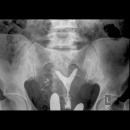

General Radiology